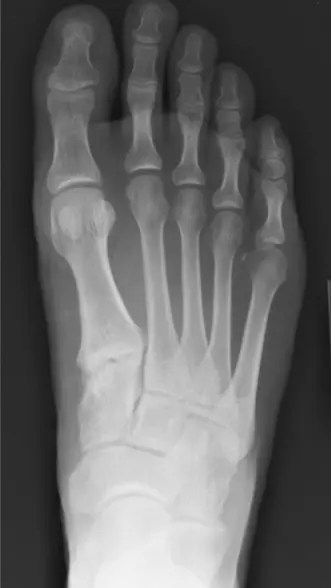

الأشعة السينية X-rays

تُعد الأشعة السينية هي الفحص الأولي الأساسي لجميع شكاوى القدم والكاحل تقريبًا.

- الصور القياسية : تُعد الصور الأمامية الخلفية (AP) والجانبية والمائلة للقدم أثناء تحمل الوزن ضرورية لتقييم محاذاة العظام وسلامتها وأي تغيرات تنكسية.

- الصور الجانبية أثناء تحمل الوزن : حاسمة لتقييم ارتفاع قوس القدم، وترهل المفصل الكاحلي الزورقي، وزاوية ميري (زاوية عظم الكاحل-المشط الأول)، وزاوية ميل العقب، وتحديد تقوس العقب للداخل في تشوهات القدم المسطحة.

- صورة سالتزمان (Saltzman view) : تُستخدم لتقييم محاذاة الكاحل الخلفي كمياً (تقوس العقب للداخل أو للخارج).

- نتائج آلام القدم الداخلية : قد تكشف الأشعة السينية عن وجود عظم زورقي إضافي، نتوءات عظمية، كسور إجهاد (مثل الزورقي، الإسفيني الإنسي)، علامات التحام الرصغ، أو مدى تشوه القدم المسطحة (مثل "علامة كثرة الأصابع" في الصورة الأمامية الخلفية، أو انكشاف رأس عظم الكاحل).

- نتائج آلام القدم الخارجية : قد تُحدد كسور قاعدة المشط الخامس (جونز، قلعية)، خلع جزئي للعظم المكعبي، كسور إجهاد في العقب، أو علامات عدم استقرار الكاحل المزمن مثل النتوءات العظمية أو ميل عظم الكاحل الطفيف.

الشكل 3: صورة شعاعية جانبية للقدم أثناء تحمل الوزن، تُظهر محاذاة العظام وارتفاع القوس وأي تغيرات تنكسية محتملة، وهي أساسية للتقييم الأولي لمسببات آلام القدم.